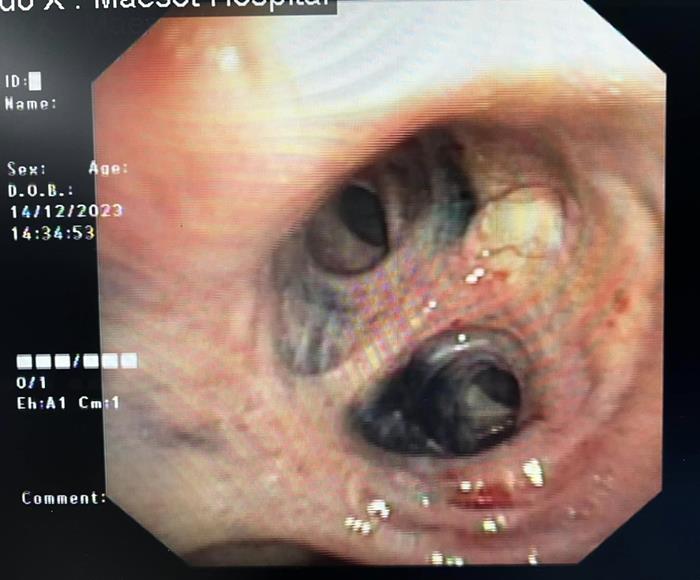

จากนั้น

แพทย์จึงตรวจสอบเชิงลึกโดยใช้วิธีส่องกล้องเข้าไปดูผ่านทางเดินหายใจ

กลับพบสิ่งที่น่าตระหนกกว่า คือ หลอดลมคนไข้รายนี้เป็นสีดำทั่ว ๆ

กระจายเป็นหย่อม ๆ หมอก็ไม่เคยเจอเคสแบบนี้ ดังนั้น

จึงมีการสอบถามประวัติคนไข้เพิ่มเติม พบว่า ผู้ป่วยรายนี้หยุดสูบบุหรี่กว่า

20 ปี แต่มีอาชีพทำไร่ทำสวน สัมผัสฝุ่นควันและมลภาวะเป็นเวลานาน

ฝุ่นถ่านดำเข้ามาในหลอดลม จนเกิดพังผืดและหลอดตีบ